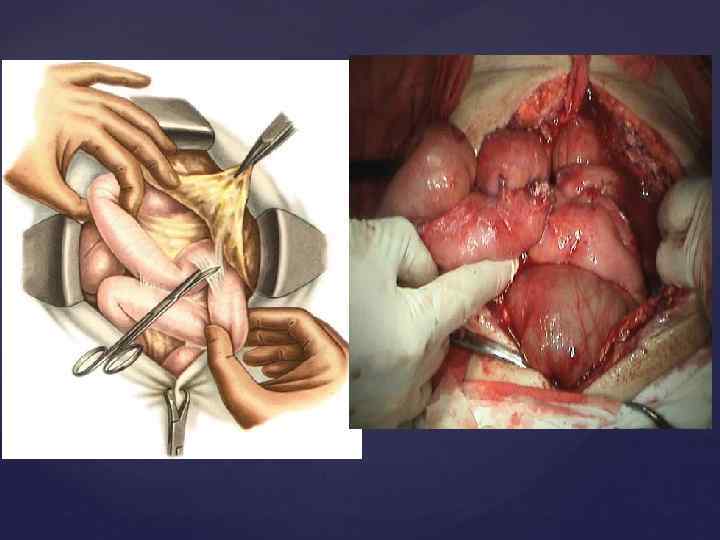

Операция жолы - орталық лапаротомия. Іш ашылғаннан соң ең алдымен ішектің түйілу себебін, оның орналасқан орнын тауып кедергі жойылады. Ішектің кедергісін анықтау үшін ең бірінші соқыр ішек тексеріледі. Егер ол өзгермесе онда кедергінің ащы ішекте орналасқандығы анық. Кедергі анықталғаннан соң ішек жара бетіне шығарылады (эвентрация). Ішек шажырқайына новокаин егіледі. Жараның бетіне шығарылған ішек дымқылданылған салфеткамен жабылады. Ішектегі нәжісті ішекті тесіп (энтеротомия), тесік арқылы өткізілген зондтың сыртқы ұшын сорғышқа не үлкен шприцке (шприц Жанэ) жалғайды. Екінші тәсіл -ішектегі нәжісті жоғарыдан төмен сауып ағызу "сауу әдісі"